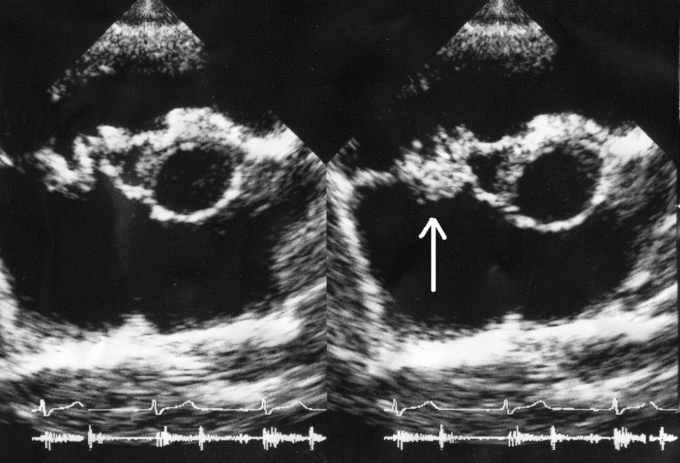

Vegetation on tricuspid valve by echocardiography. Arrow denotes the vegetation.